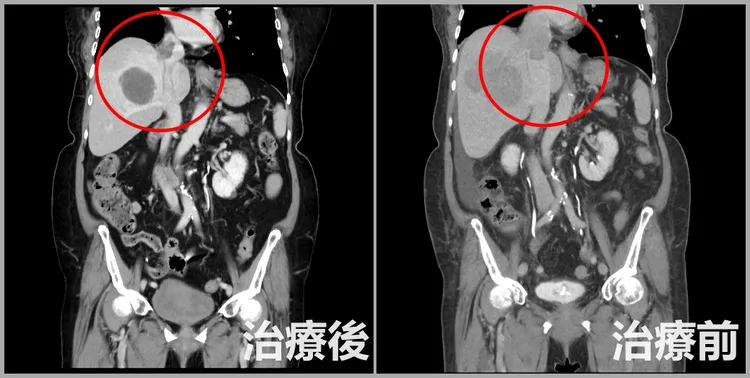

王博民說,由於肝癌發現時已經是晚期,因此立即安排電腦斷層掃描(CT)檢查擴散狀況,發現癌細胞從最底下的肝門靜脈、下腔靜脈,一路爬到右心房,「幾乎能塞的都塞住了」,可說是肝癌合併血栓病症中最嚴重的情形,找到造成腹水、狂喘的元兇。

由於患者年齡偏高,且血栓位置幾乎侵犯整個下心房,若貿然手術,術後恐怕難以支撐,因此評估後,決定採用非侵入式的好神刀放射治療對抗癌細胞,約兩週療程就打通肝門靜脈,右心房血栓長度也明顯變小,僅剩1公分多,大幅改善下肢水腫、猛喘等症狀,之後搭配標靶藥物及免疫治療,狀況逐漸改善,也讓患者保持抗癌信心。

患者因肝臟腫瘤往上擴散壓迫到右心房,經採用三合一治療後,成功縮小腫瘤。亞大附醫提供